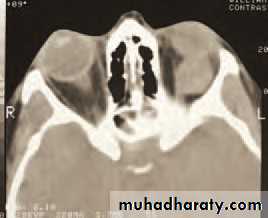

• An MRI or CT scan is helpful in diagnosis and in planning treatment (Fig. 4.2). The condition usually responds to intravenous broad spectrum antibiotics. It may be necessary to drain an abscess or decompress the orbit particularly if the optic nerve is compromised. Optic nerve function must be closely watched, monitoring acuity, colour vision and testing for a relative afferent pupillary defect. Orbital decompression is usually performed with the help of an ENT specialist.

(b)• Fig. 4.2 (a) The clinical appearance of a patient with right orbital cellulitis.

• (b) A CT scan showing a left opaque ethmoid sinus and subperiosteal orbital abscess.